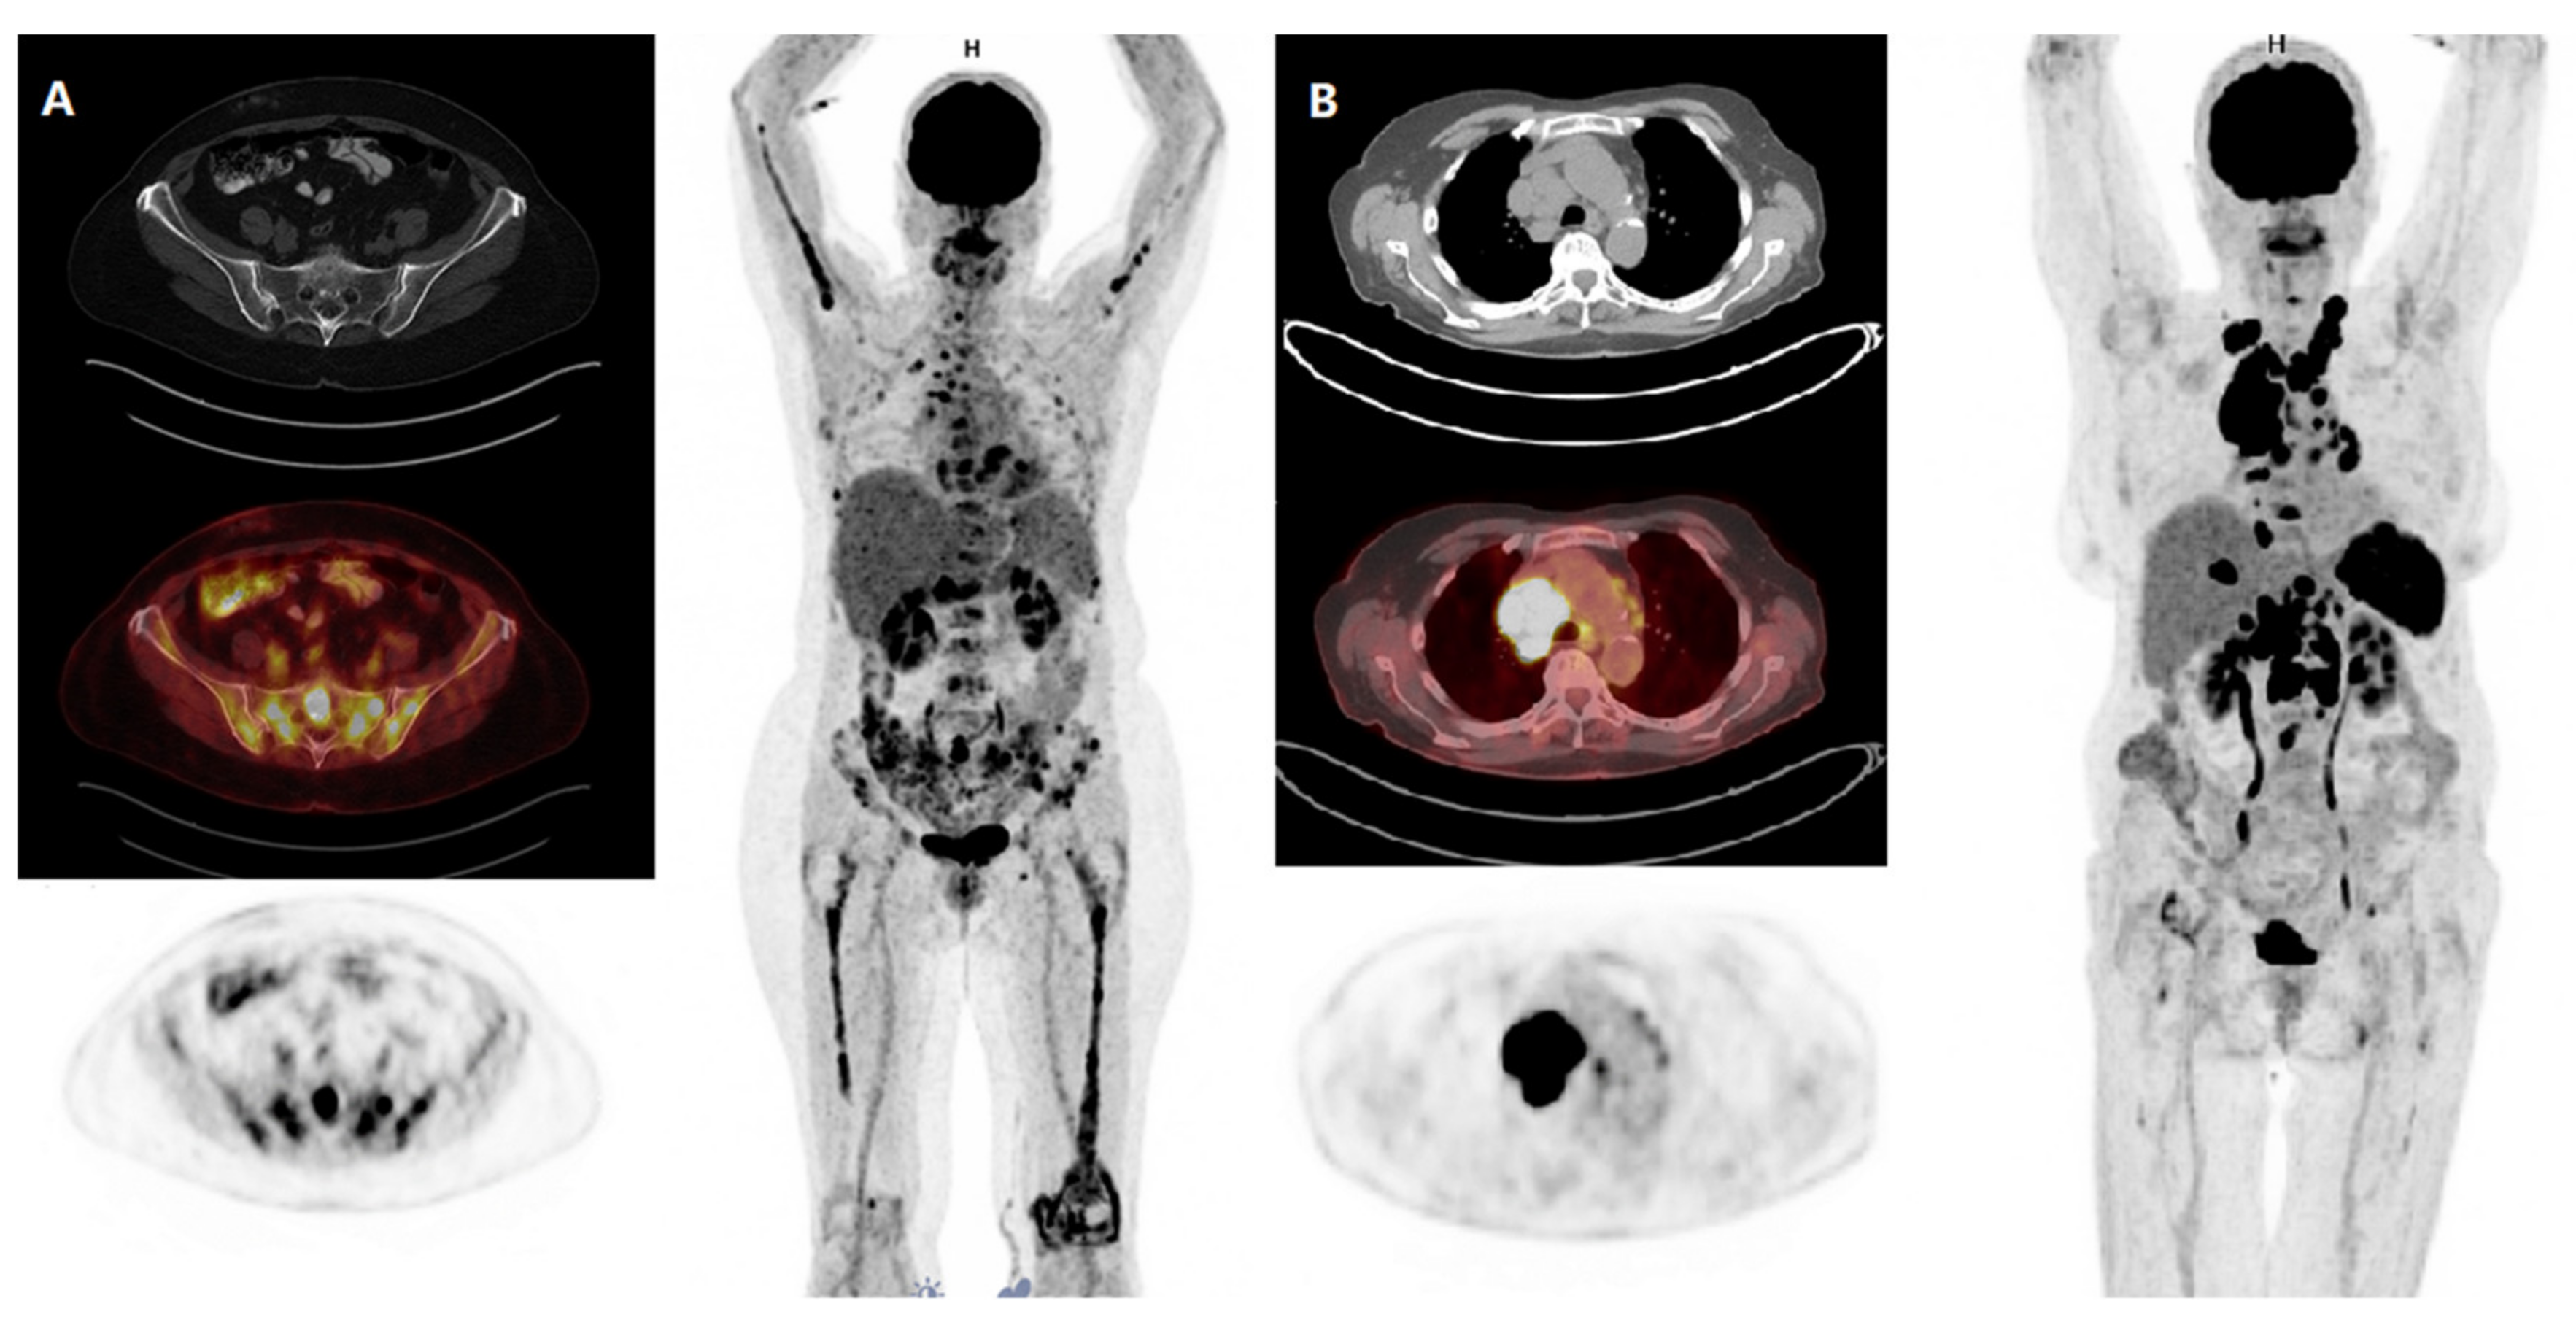

Lymph nodes can light up for various reasons on a PET with infection being the most common cause. FDG PETCT has become an important modality in the evaluation of lymph nodes in oncology patients including the central role FDG PETCT plays in managing patients with lymphoma and the ability for FDG PET to detect nodal metastases in subcentimeter nodes which may be overlooked on CT or magnetic resonance. I have been reading this board for a while even before I really had a diagnosis and have seen posts from several people who have had nodes show up enlarged lit with a pet scan etc and they have turned tout to be false alarms.

I also have other problems like severe dry mouth mass in lung severe allergies RA that are all igg4 complications. Results of PET-CT were compared with histopathology of the lymph nodes and sensitivity specificity positive predictive value negative predictive value and accuracy were calculated. If mediastinal lymph nodes are suspected an individual may have to undergo a CT scan for confirmation.

All patients underwent 18 F-FDG PET-CT scan for evaluation of mediastinal lymph nodes. Regional lymph node classification for lung cancer staging adapted from the American Thoracic Society mapping scheme. Drop right to Impression it basically restates Findings in more general terms.